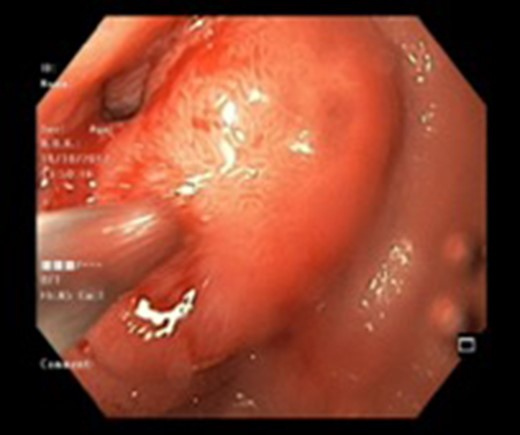

Endoscopic view of a submucosal mass in the second part of the duodenum.

| Case 1 | 30/M | 3 months | Vomiting, Malena | Well defined rounded hypodense submucosal lesion in second part of duodenum (Fig. 1) | Smooth mucosal bulge likely due to submucosal lesion in D2 with difficulty in negotiating scope beyond (Figs 2 and 3) | Normal duodenal mucosal fragments with mild lympho-mono nuclear cell infiltrate in the lamina propria | Pancreaticoduodenectomy | 2 | 2 days | 6 |

Endoscopy can localize the lesion; however, biopsies are usually negative. Only a deep endoscopic or a surgical biopsy provides adequate tissue because the Brunner’s gland proliferations are usually covered by normal mucosa [10] (Figs 6 and 7). It is prudent to include a Brunner gland hyperplasia in a differential diagnosis while evaluating a duodenal mass, since it has varied presentation and bleeding is a common clinical sign masquerading other gastrointestinal conditions, e.g. gastrointestinal stromal tumours.